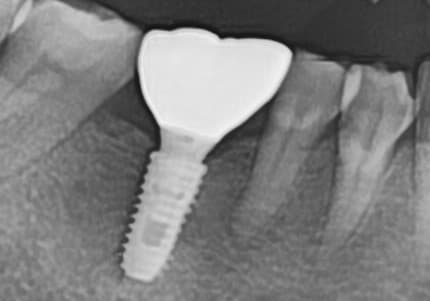

"骨质严重流失

牙龈治疗后骨质得到恢复"

Before

After

严重牙龈病导致骨质大量流失的状态

牙龈治疗和骨移植再生后植入种植牙